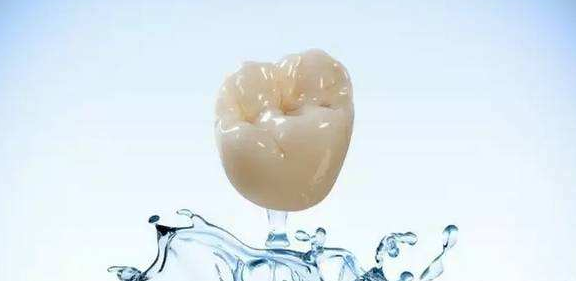

在廊坊,全瓷冠崩瓷的原因有哪些?

在廊坊,全瓷冠绷瓷的原因一般有以下几点:

1、牙备空间不够

全瓷冠咬合面瓷层厚度在后牙应该为2~2.5mm,瓷层厚度不足或过厚都会造成崩瓷。其实瓷层厚度的数值大家都知道,只是在临床上由于观察角度或观察经验欠佳造成误判。